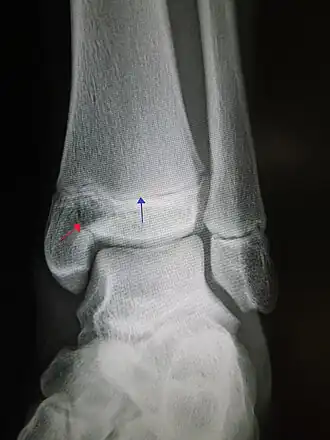

Рентгеновский снимок голеностопного сустава с эпифизеолизом медиальной лодыжки. Красная стрелка - линия перелома, синяя указывает на ростковую зону.